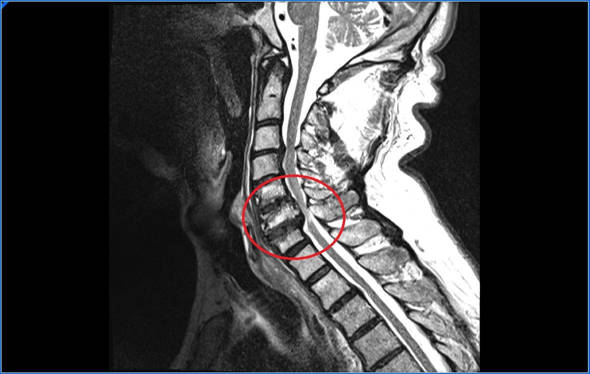

- Resonancia magnética. Es la prueba principal que nos ayuda a llegar al diagnóstico, con la resonancia confirmaremos nuestras sospechas diagnósticas, en la RMN veremos el estado de los discos, la presencia o no de hernias cervicales o la existencia de una mielopatía cervical

Mielopatía cervical

La mielopatía cervical se produce cuando la hernia cervical comprime y produce una afectación de la médula espinal. Cuando se tienen una mielopatía cervical se afectan tanto los brazos como las piernas. Debido a la falta de sensibilidad en las piernas aumentamos la base de sustentación y tenemos alteraciones en el equilibrio, tendremos debilidad y podemos llegar a tener alteraciones en los esfínteres. En las manos notaremos torpeza y dificultad para coger objetos o abrir y cerrar las manos con rapidez.